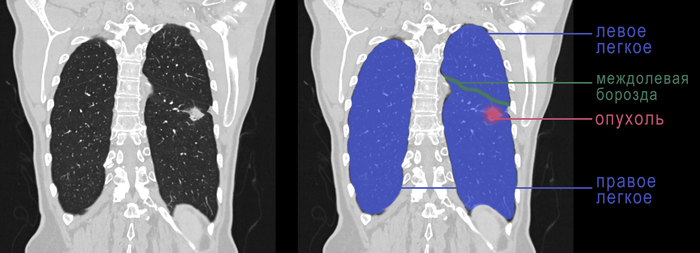

У второго пациента в 2010 году уже был рак желудка, по поводу которого успешно проведено хирургическое и химиотерапевтическое лечение. Пациент жив на протяжении 11 лет. Однако коронавирусная инфекция принудила пациента сделать КТ, на которой выявлено новообразование нижней доли левого легкого:

КТ-картина однозначно говорила нам о том, что опухоль недобрая. Поэтому мы не заморачивались с биопсией и сразу пошли на операцию. Пациенту выполнена нижняя лобэктомия слева, то есть удаление нижней доли левого легкого, что составляет половину от легкого и 25% всего легочного объема. При гистологическом исследовании у пациента диагностирована первичная аденокарцинома легкого без метастазов внутри легкого и в медиастинальных лимфатических узлах, то есть речь идет о раке легкого I стадии. Пациент победил второй рак в своем организме и отправился домой под динамическое наблюдение.